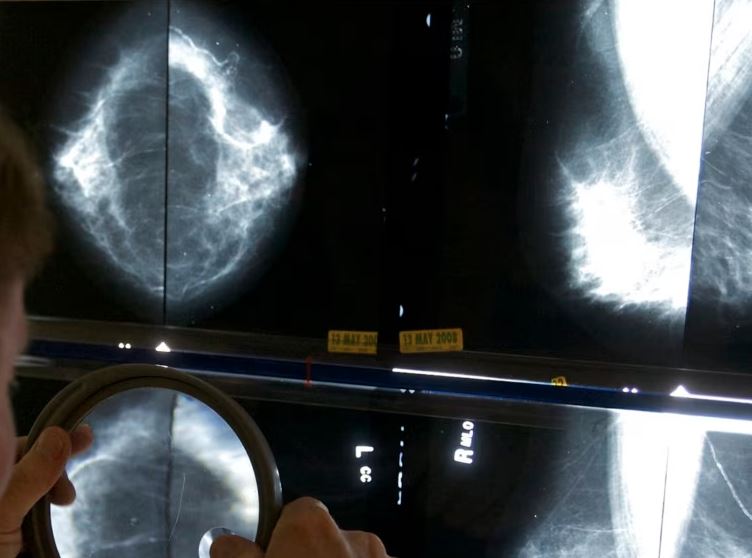

Gratë që kryejnë operacion për kancerin e gjirit shpesh i nënshtrohen edhe asaj që quhet biopsi e nyjeve limfatike qendrore, ku hiqen disa nyje limfatike në sqetull për të kontrolluar për përhapjen e kancerit.

Ajo bën mamografi çdo gjashtë muaj për të mbajtur nën kontroll kancerin e llojit DCIS në gjirin e djathtë, i cili nuk është përhapur. Mamografitë vunë re një kancer të vogël në gjirin tjetër të saj në vitin 2023, të palidhur me DCIS. Ajo iu nënshtrua një operacioni për heqjen e tij.